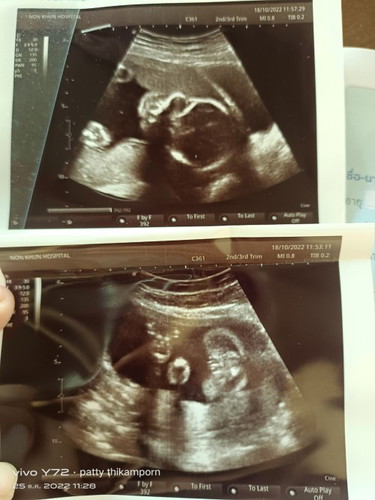

แม่ๆช่วยดูหน่อยจ้า ดูยังไงให้น้องเป็นผู้หญิง หมอบอกผู้หญิง80% รอซาวด์อีกที31นี้

รูปข้างล่างป่ะค่ะ เหมือนเป็นก้นน้อง ถ้าใช่เราก็ว่าผู้ญ ค่ะ อันนี้ของเรา